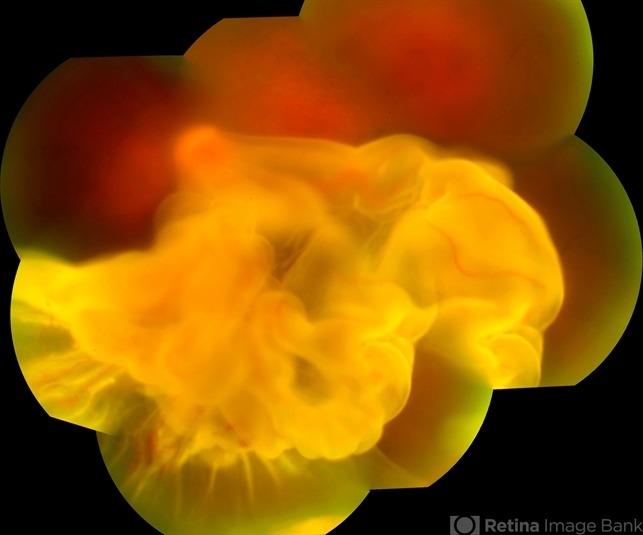

This patient really has a RD and has always been controlled. Even so, there was a worsening of the vision in which it evolved into a detachment. In the Ultrasson examination it shows up to a closed funnel pattern. -

Fundus camera Topcon TRC-50 DX, Imaginet 5.0, angle de 50 graus. Flash 36 / Mosaic with 10 images. - Description

- A 42-year-old patient complained of low vision in the left eye. In retinal mapping and background color photography, extensive retinal detachment was observed.